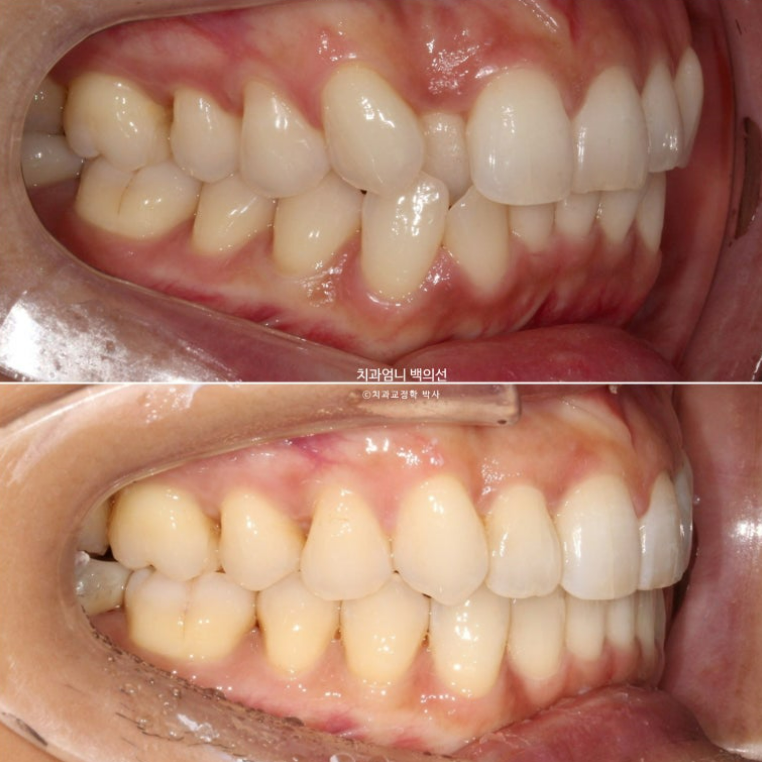

깔끔하고 적절한 스마일라인

덧니쪽으로 쏠려있던 앞니 중심선이 코와 인중이 맞게 되었습니다.

앞니각도도 적절합니다.

원래 예뻤던 입매는 잘 유지가 되었습니다.

치근흡수는 없고 치근평행도는 좋습니다.

인비절라인 교정은 철사 브라켓 교정에 비해서 치아에 가해지는 힘이 약한 만큼 경험상 오래 걸리는 교정이여도 전반적으로 치근흡수는 거의 없습니다.

1년 6개월간 변화로 입술이 좀더 편하게 다물리게 되었습니다.